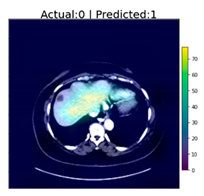

| 6 | ![]() | No Tumor | Has Tumor | Has Tumor | Yes |

| 15 | ![]() | No Tumor | Has Tumor | No Tumor (Cyst) | Some |